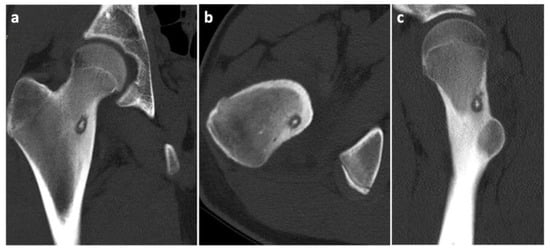

Figure 2.

CT scans of the osteoid osteoma in different projections. (a) Frontal view; (b) Transverse view; (c) Sagittal view.

To prove the diagnosis of OO, a CT scan of the affected area was taken. The condition was consulted with a neurologist, who found decreased reflexivity in the L2–L4 myotomes, and, therefore, recommended a lumbar spine MRI to rule out any spinal lesions (e.g., a tumor). No such affection was found. Even though our diagnostic algorithm was not standard (among other things, due to the fact that the patient was referred to our workplace only after the MRI was performed), we arranged the individual diagnostic steps and the Figure 1, Figure 2 and Figure 3 (i.e., clinical examination–CT–MRI) in the correct order for better clarity.